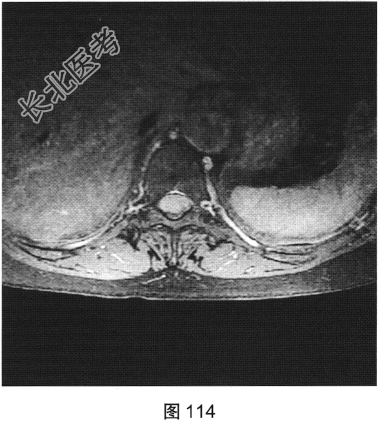

- [材料题] 患者女性,59岁,无明显诱因出现腰背部疼痛伴双下肢麻木1年,久行、久坐、久站或咳嗽、排便时疼痛加重,休息后症状缓解,1个月前腰背部麻木疼痛突发加重,行走100米既感疼痛难忍,伴双下肢无力疼痛。查体:脊柱无明显侧弯,相当于T₁₀平面以下感觉减退,腰椎活动度受限,无紧张,棘突旁压痛、叩痛,向双下肢放射。挺腹试验阳性,跟臀试验(+),双侧直腿抬高试验(一),双下肢小腿外侧、足背感觉稍差,双侧

背伸肌肌力4级;肌张力正常,双侧巴宾斯基征可疑阳性。实验室检查:人类白细胞抗原B27阴性(一),RF<10U/ml(正常值0~15U/ml)。

- 简答题2、患者行MRI检查,如图111~图114所示。根据患者病史及影像学检查,请问其最可能的诊断是什么?